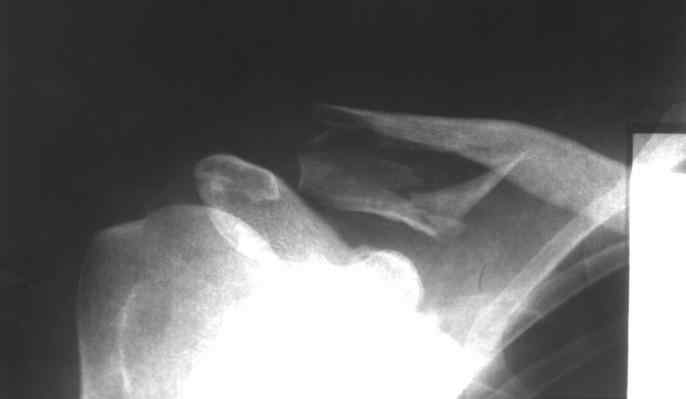

Оскольчатый перелом ключицы |

Пациент,32 года, травма - падение с высоты на правое плечо. Прооперирован 20.05.08.... Ad oculus, при ревизии перелома, многооскольчатый перелом, акромиально-ключичное сочленение сохранено. Коллеги, прошу высказать ваше мнение по поводу данного случая: Выбор метода? качество остеосинтеза? ваш вариант лечения? Возможные осложнения? Спасибо!

http://В данном случае применениtй крючковидной пластины вполне оправдано. К сожадению выбран неправилиный размер фиксатора. Удлиненный вариат пластины решил бы все проблемы.

Здесь чистый перелом ключицы, который прекрасно срастается без операции. А связки AKC целы. Хотя такое повреждение можно лечить как повреждение АКС. Например, аппаратом. Презентация на эту тему лежит тут (4,7 Mb).

Не согласен. Лечить без операции, конечно. можно, но переломы ДИСТАЛЬНОГО отдела ключицы дают очень высокий процент несращений, потому все-таки страндартная рекомнедация - оперировать. можно лентой, спицами чрезсуставно, пластинами - как угодно

Плохо срастался бы "короткий" перелом с отрывом связок или сразу медиальнее их. А такой, как здесь, с горизонтальным раскалыванием дистального конца ключицы, имеет большую площадь излома, соответственно, и костеобразования. Ни разу не встречал несращения при подобном по форме переломе.